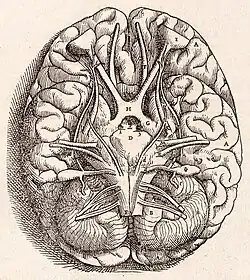

- A revolution took place in both neurology in particular and in anatomy in general when Andreas Vesalius published his De humani corporis fabrica in 1543. It includes detailed images depicting the ventricles, cranial nerves, pituitary gland, meninges, structures of the eye, the vascular supply to the brain and spinal cord, and an image of the peripheral nerves.[16] Vesalius, unlike many of his contemporaries, did not subscribe to the then common belief that the ventricles were responsible for brain function, arguing that many animals have similar systems of ventricles to those of humans but no true intelligence.[17] It appears that he rarely removed the brain from the skull before cutting it, most of his diagrams showing the brain sitting inside a severed head.[18]

In 1549, Jason Pratensis published De Cerebri Morbis, a volume devoted to neurological diseases, in which he discussed symptoms, as well as ideas from Galen and other Greek, Roman, and Arabic authors.[19] Thomas Willis in 1664 published his Anatomy of the Brain, followed by Cerebral Pathology in 1667. He removed the brain from the cranium and was able to describe it more clearly, setting forth the circle of Willis, the circle of vessels that enables arterial supply of the brain. He had some notions as to brain function, including a vague idea as to localization and reflexes, and described epilepsy, apoplexy, and paralysis. He was among the first few authors to use the word "neurology," after anatomist Jean Riolan the Younger in 1610.[20]